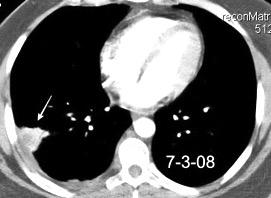

Nefrectomia derecha en 1996 por adenocarcinoma renal. Reseccion de metastasis pulmonar en LSI de carcinoma renal. Sospecha de nueva metástasis.